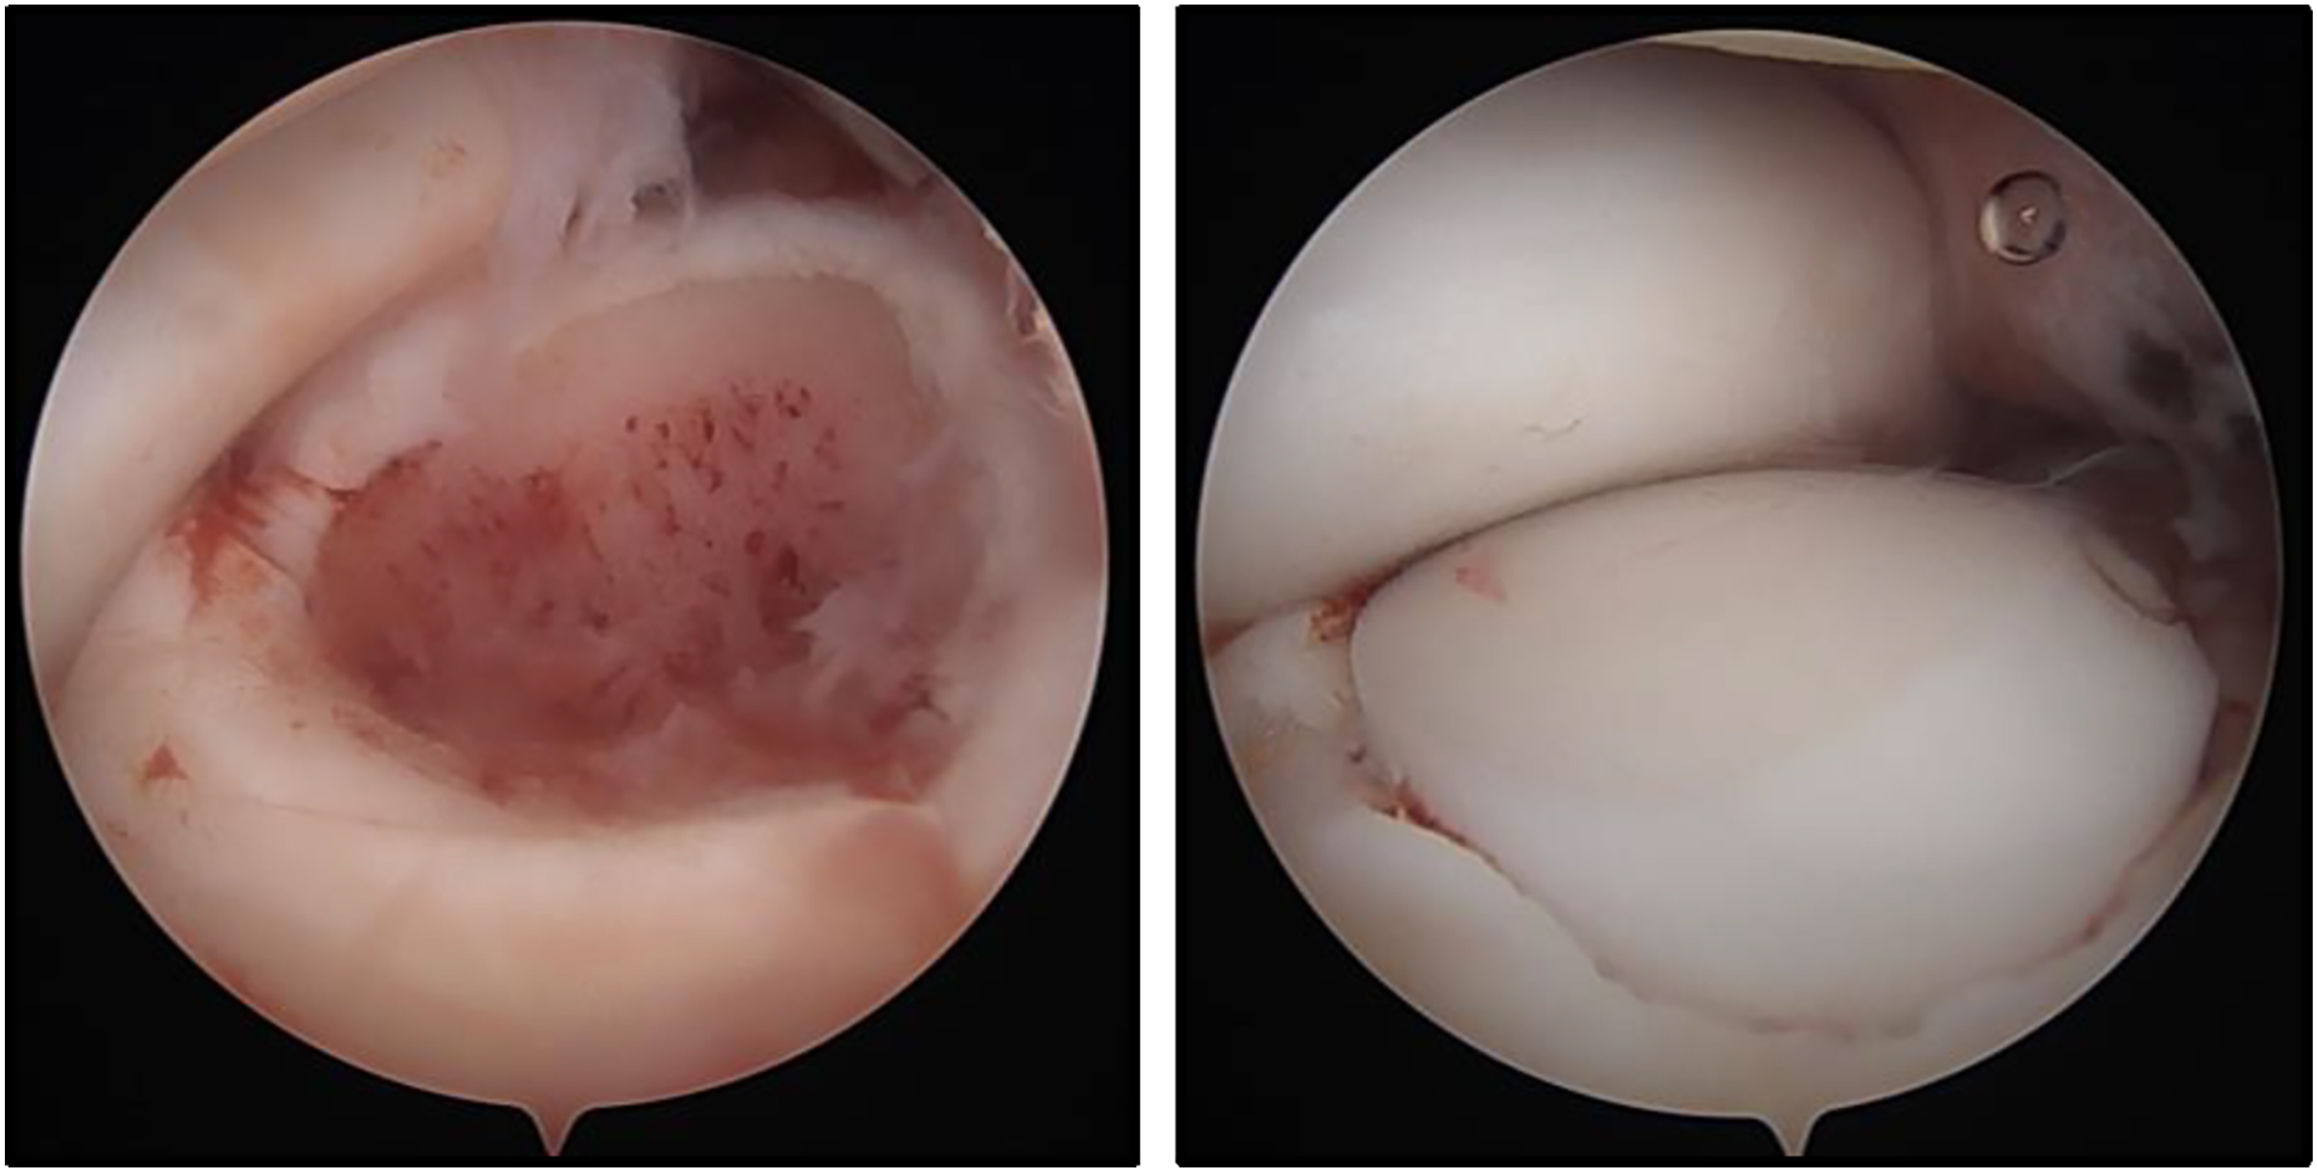

Numerous authors have concluded that many capitellar OCD lesions lack innate healing potential and thus conservative care may lead to poor outcomes especially in high-risk, overhead athletes trying to RTS. , Surgical management of OCD is largely guided by size and location of the lesion. Predictors of poor outcomes with nonoperative care are unstable lesions, older age, longer duration of symptoms, closed lateral epicondylar physes, higher stage lesion classification findings, larger lateral lesions (especially uncontained lesions—lesions extending lateral to the radial head center line and including the lateral margin ; Fig. 5 ), as well as radiocapitellar incongruity and radial head hypertrophy/migration. , Surgical options include arthroscopic debridement, drilling/microfracture and loose body (LB) removal for smaller lesions, and fragment fixation and open complex reconstruction procedures for larger lesions.

With the high demand of the throwing athlete and the average-to-moderate outcomes of arthroscopic debridement and drilling, complex cartilage reconstruction and restoration procedures may be the preferred option for large unstable lateral lesions. At the forefront of these procedures is osteochondral autograft (OAT) and allograft transplantations ( Fig. 6 ). Autograft harvest sites have included the ipsilateral or contralateral elbow and knee (lateral trochlea, notch, costochondral), and allograft donors have ranged from precut fresh osteochondral plugs or knee condyle/trochlea to multiple other sources such as the humeral head, distal humerus, femoral head, and talar head. In a systematic review from 2016 comparing RTS rates in athletes (primarily baseball players and gymnasts) undergoing OCD debridement, fixation or OAT procedures, Westermann and colleagues found that the return to the highest preoperative level of sport was most common after OAT (94%). They also demonstrated that fragment fixation had a lower RTS and higher reoperation rate than both debridement and OATS. Since that time, multiple other systematic reviews and studies have also supported high (>90%) successful RTS and graft incorporation rates, as well as reliable outcomes with few complications and low donor-site morbidity. ,